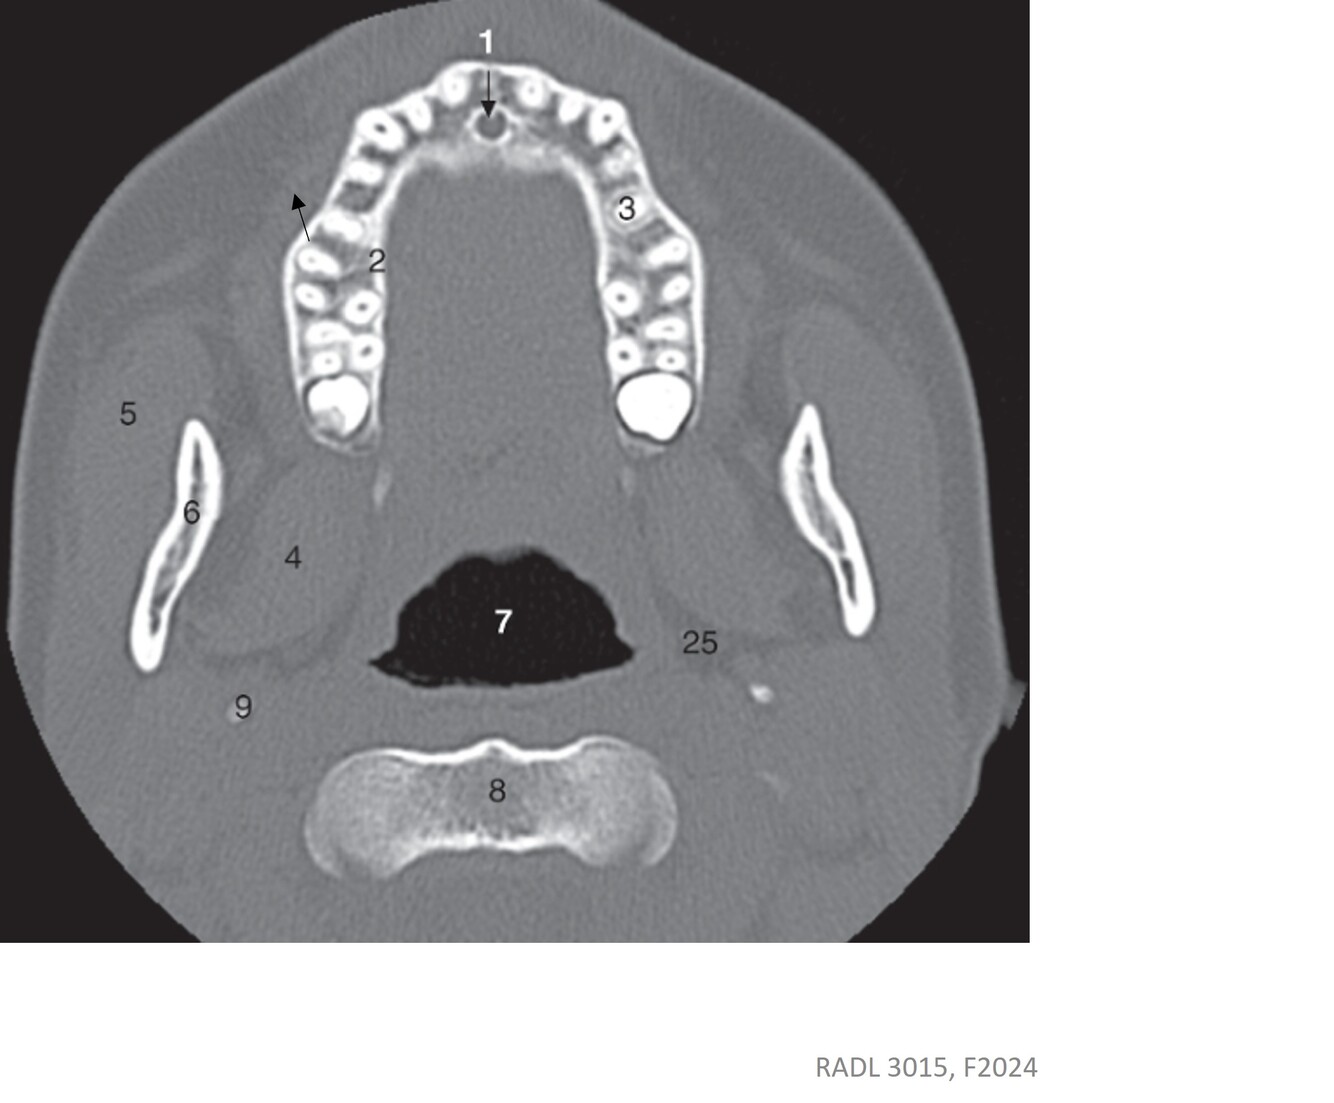

3

Label 2,5,6,7,8,9

A

2=Alveolar process of maxilla

5=Rt. Masseter muscle

6=Rt. Ramus of mandible

7=Oropharynx

8=Body (C2)

9=Styloid process (Lt Temporal bone)